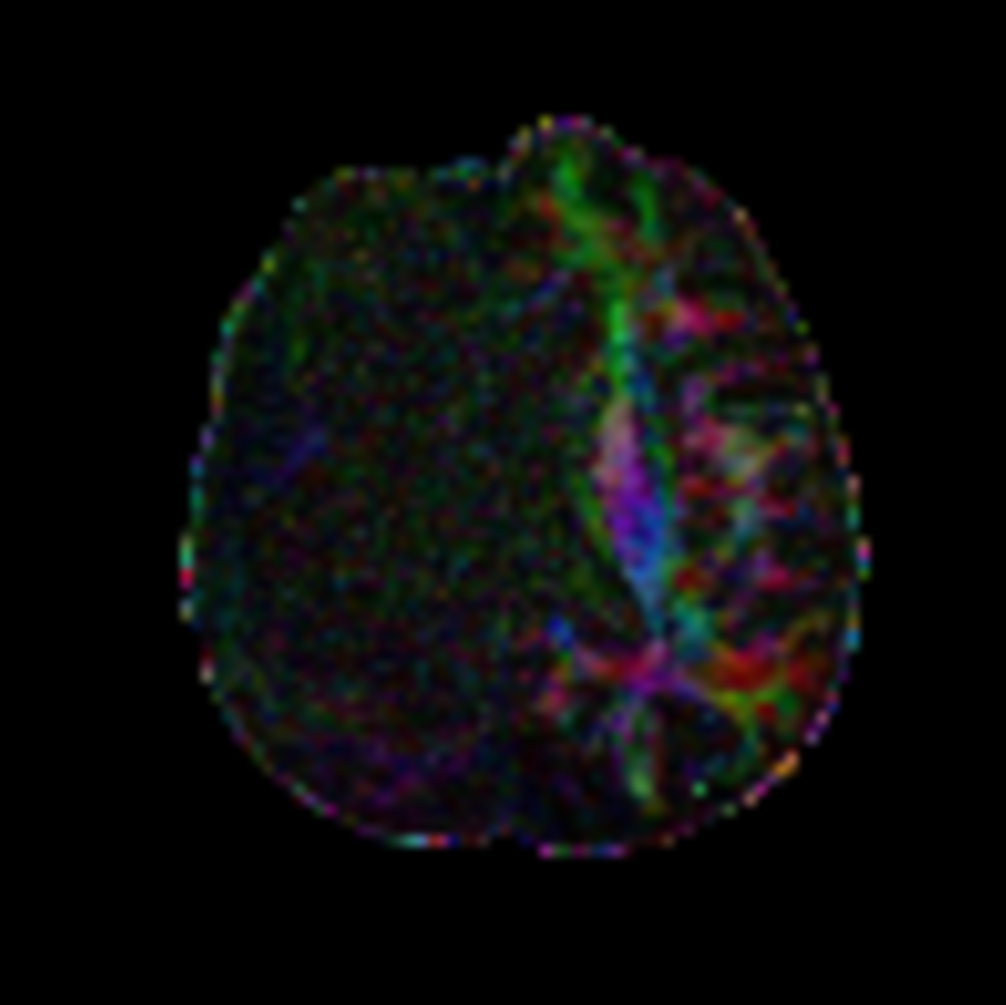

Axial DTI FiberTrak (32 directions)

DTI FiberTrak (32 directions)